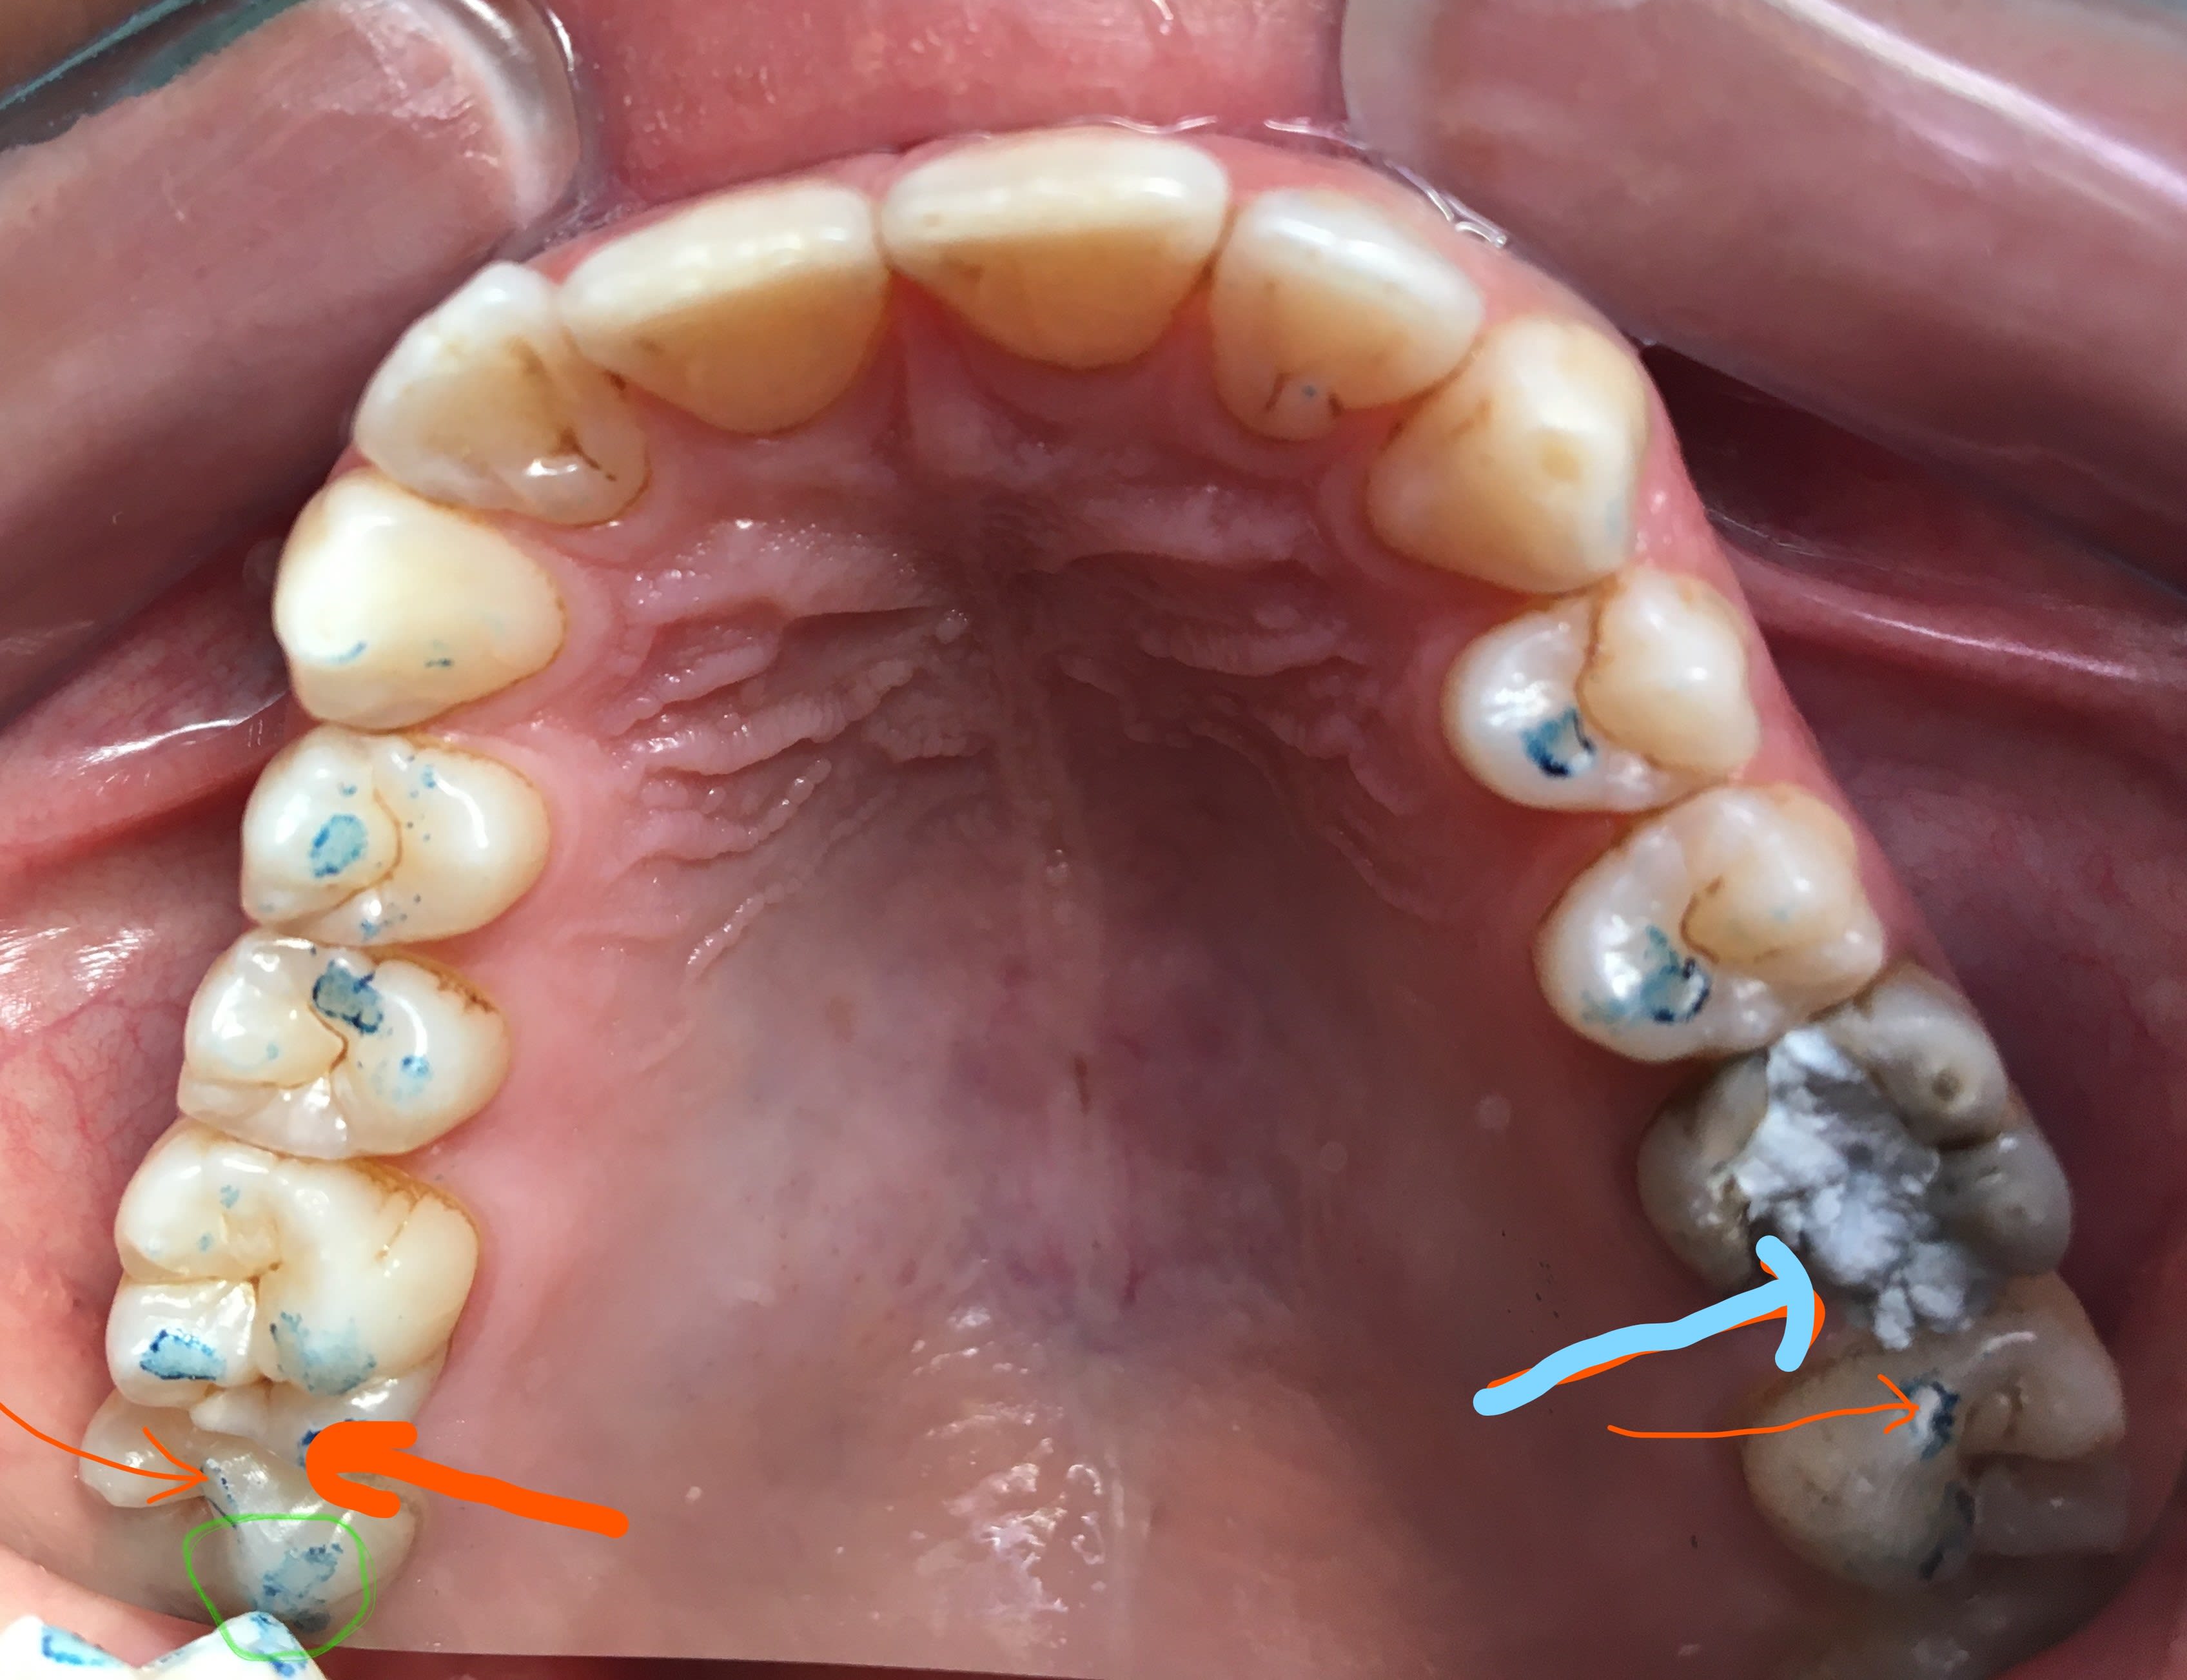

" alors comme on se cague des lateralités , et du centrage , on regarde les soit disant mvts fonctionnels , et on en néglige le calage . surtout le calage inter proximal avec ses cretes marginales . "

2 zpa9ex - Eugenol

Inked1 li uqhuiy - Eugenol